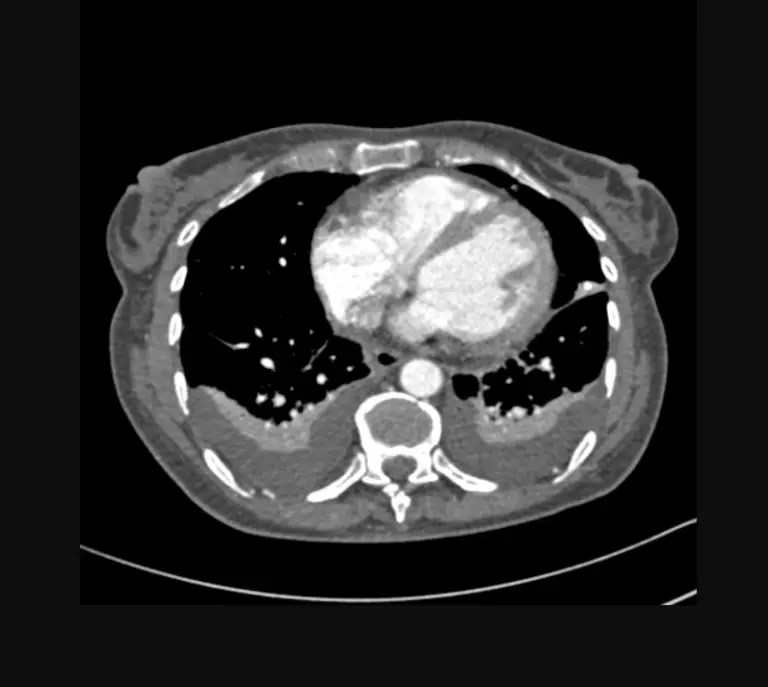

We are on a mission to change how our students learn about anatomic pathology by using real CT and MRI images to create models to better teach our students.

We are creating a 3D printed library of anatomic models of pathology for our medical students.

At the CIAV we have to see it to believe it. We believe that visualization and tactile manipulation of pathological anatomic specimens is key to sustained knowledge acquisition.